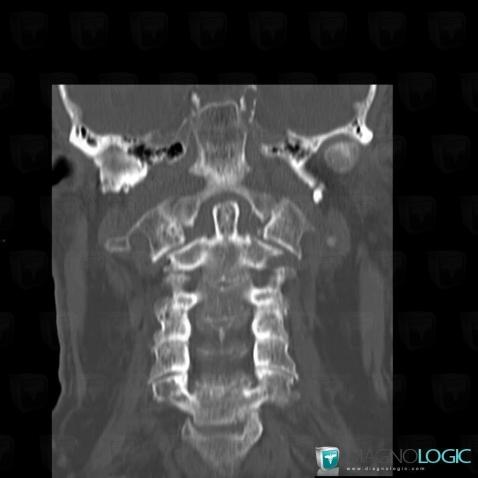

Vertebral fracture, Vertebral body / Disk, CT

Here is the specific information in the key image above:

- Diagnosis Vertebral fracture, Location(s) Vertebral body / Disk, with gamuts